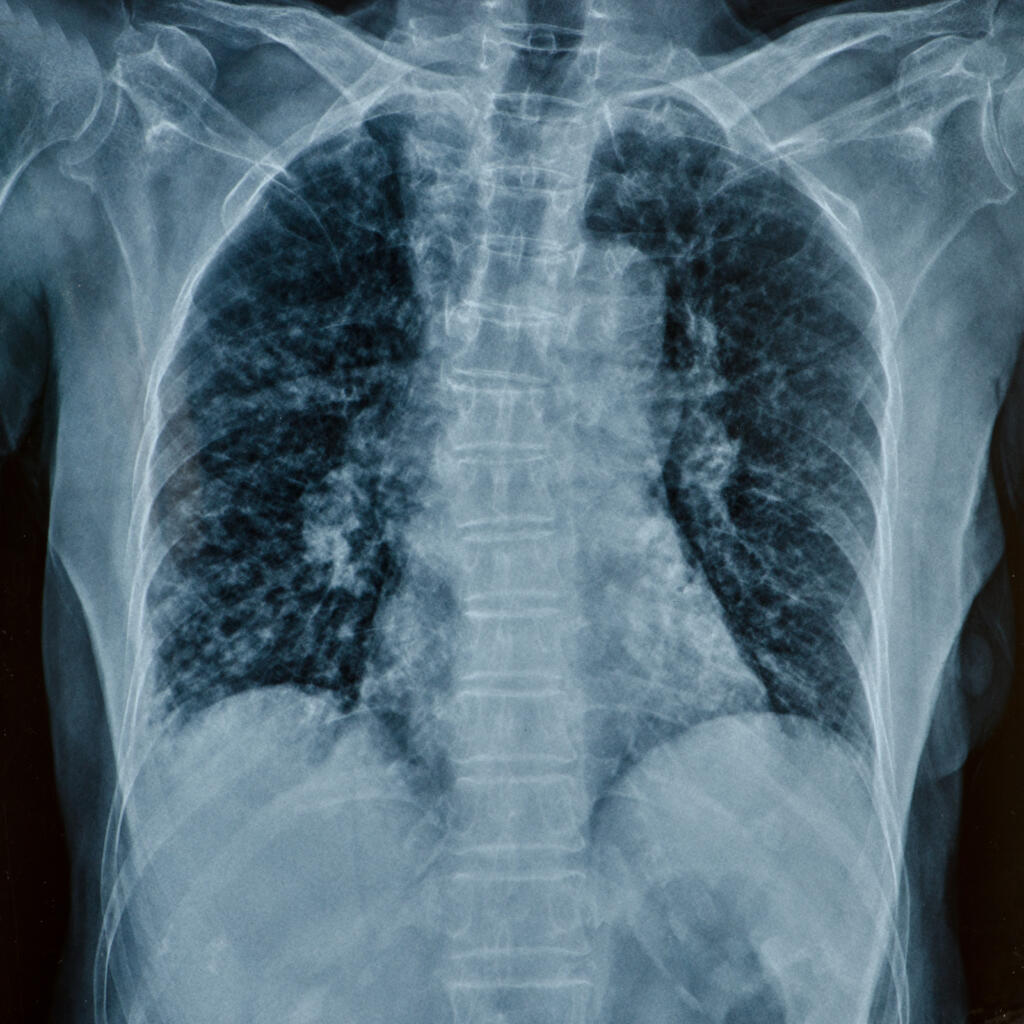

Günümüzde check-up (tarama) programlarının ve bilgisayarlı tomografinin (BT) yaygınlaşmasıyla birlikte, “akciğerde nodül” (halk arasındaki tabiriyle akciğerde leke) saptanma oranı oldukça artmıştır. Polikliniklere başvuran hastaların en büyük endişesi, raporda gördükleri bu nodülün doğrudan kanser anlamına geldiğidir.

Akciğer nodülü, akciğer dokusu içinde yerleşmiş, çapı genellikle 3 cm’den küçük olan yuvarlak veya oval şekilli lekelerdir. Türkiye gibi tüberküloz (verem) ve çeşitli akciğer enfeksiyonlarının geçmişte sık görüldüğü ülkelerde, akciğerde kireçlenmiş (kalsifik) nodüllere rastlamak oldukça doğaldır. Bunlar genellikle vücudumuzun eski bir savaştan kalan “yara izleri” gibidir ve tedavi gerektirmezler.

Ayrıca özellikle kadın hastalarda sigara içmiyor olsalar bile, tesadüfen çekilmiş bir akciğer tomografisinde buzlu cam nodülü (GGO) dediğimiz sahalara rastlanabilir. Bu alanlar ciltteki benler gibi düşünülmelidir. Radyolojik tecrübesi olan gözler tarafından uzun yıllar takibi gerekli olabilir.